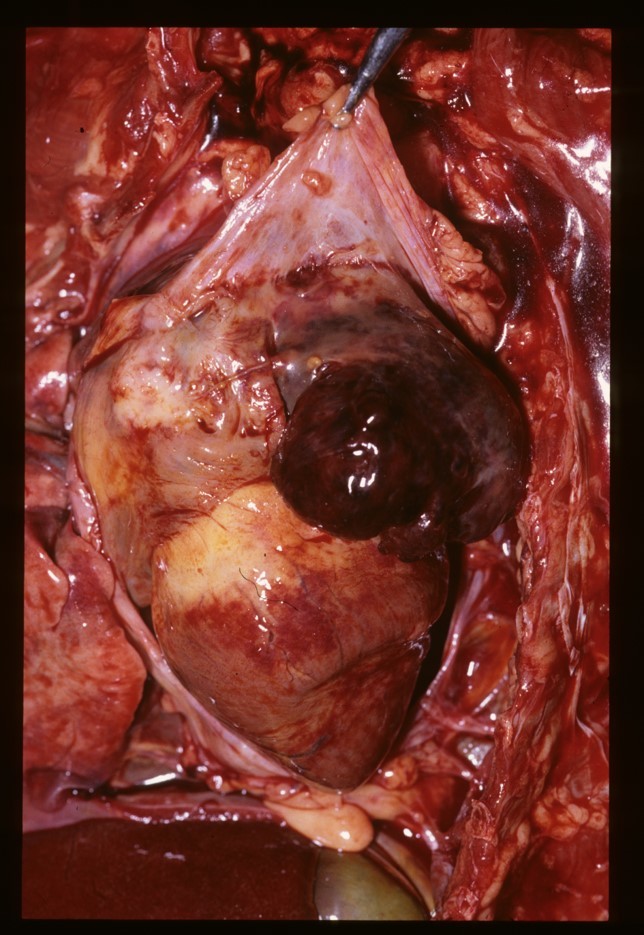

What can be seen in these images?

Dog that had thoracic surgery, has radio dense mass in throax which was displacing heart – chest opened up (middle pic) and heart put back in right place. Mass ended up being a large haemangiosarcoma – 6 months later, it reoccurred